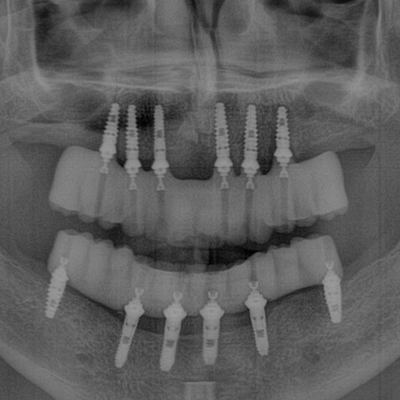

• Dental X-Ray Photo

• Panoramic Imaging for full-mouth diagnostics